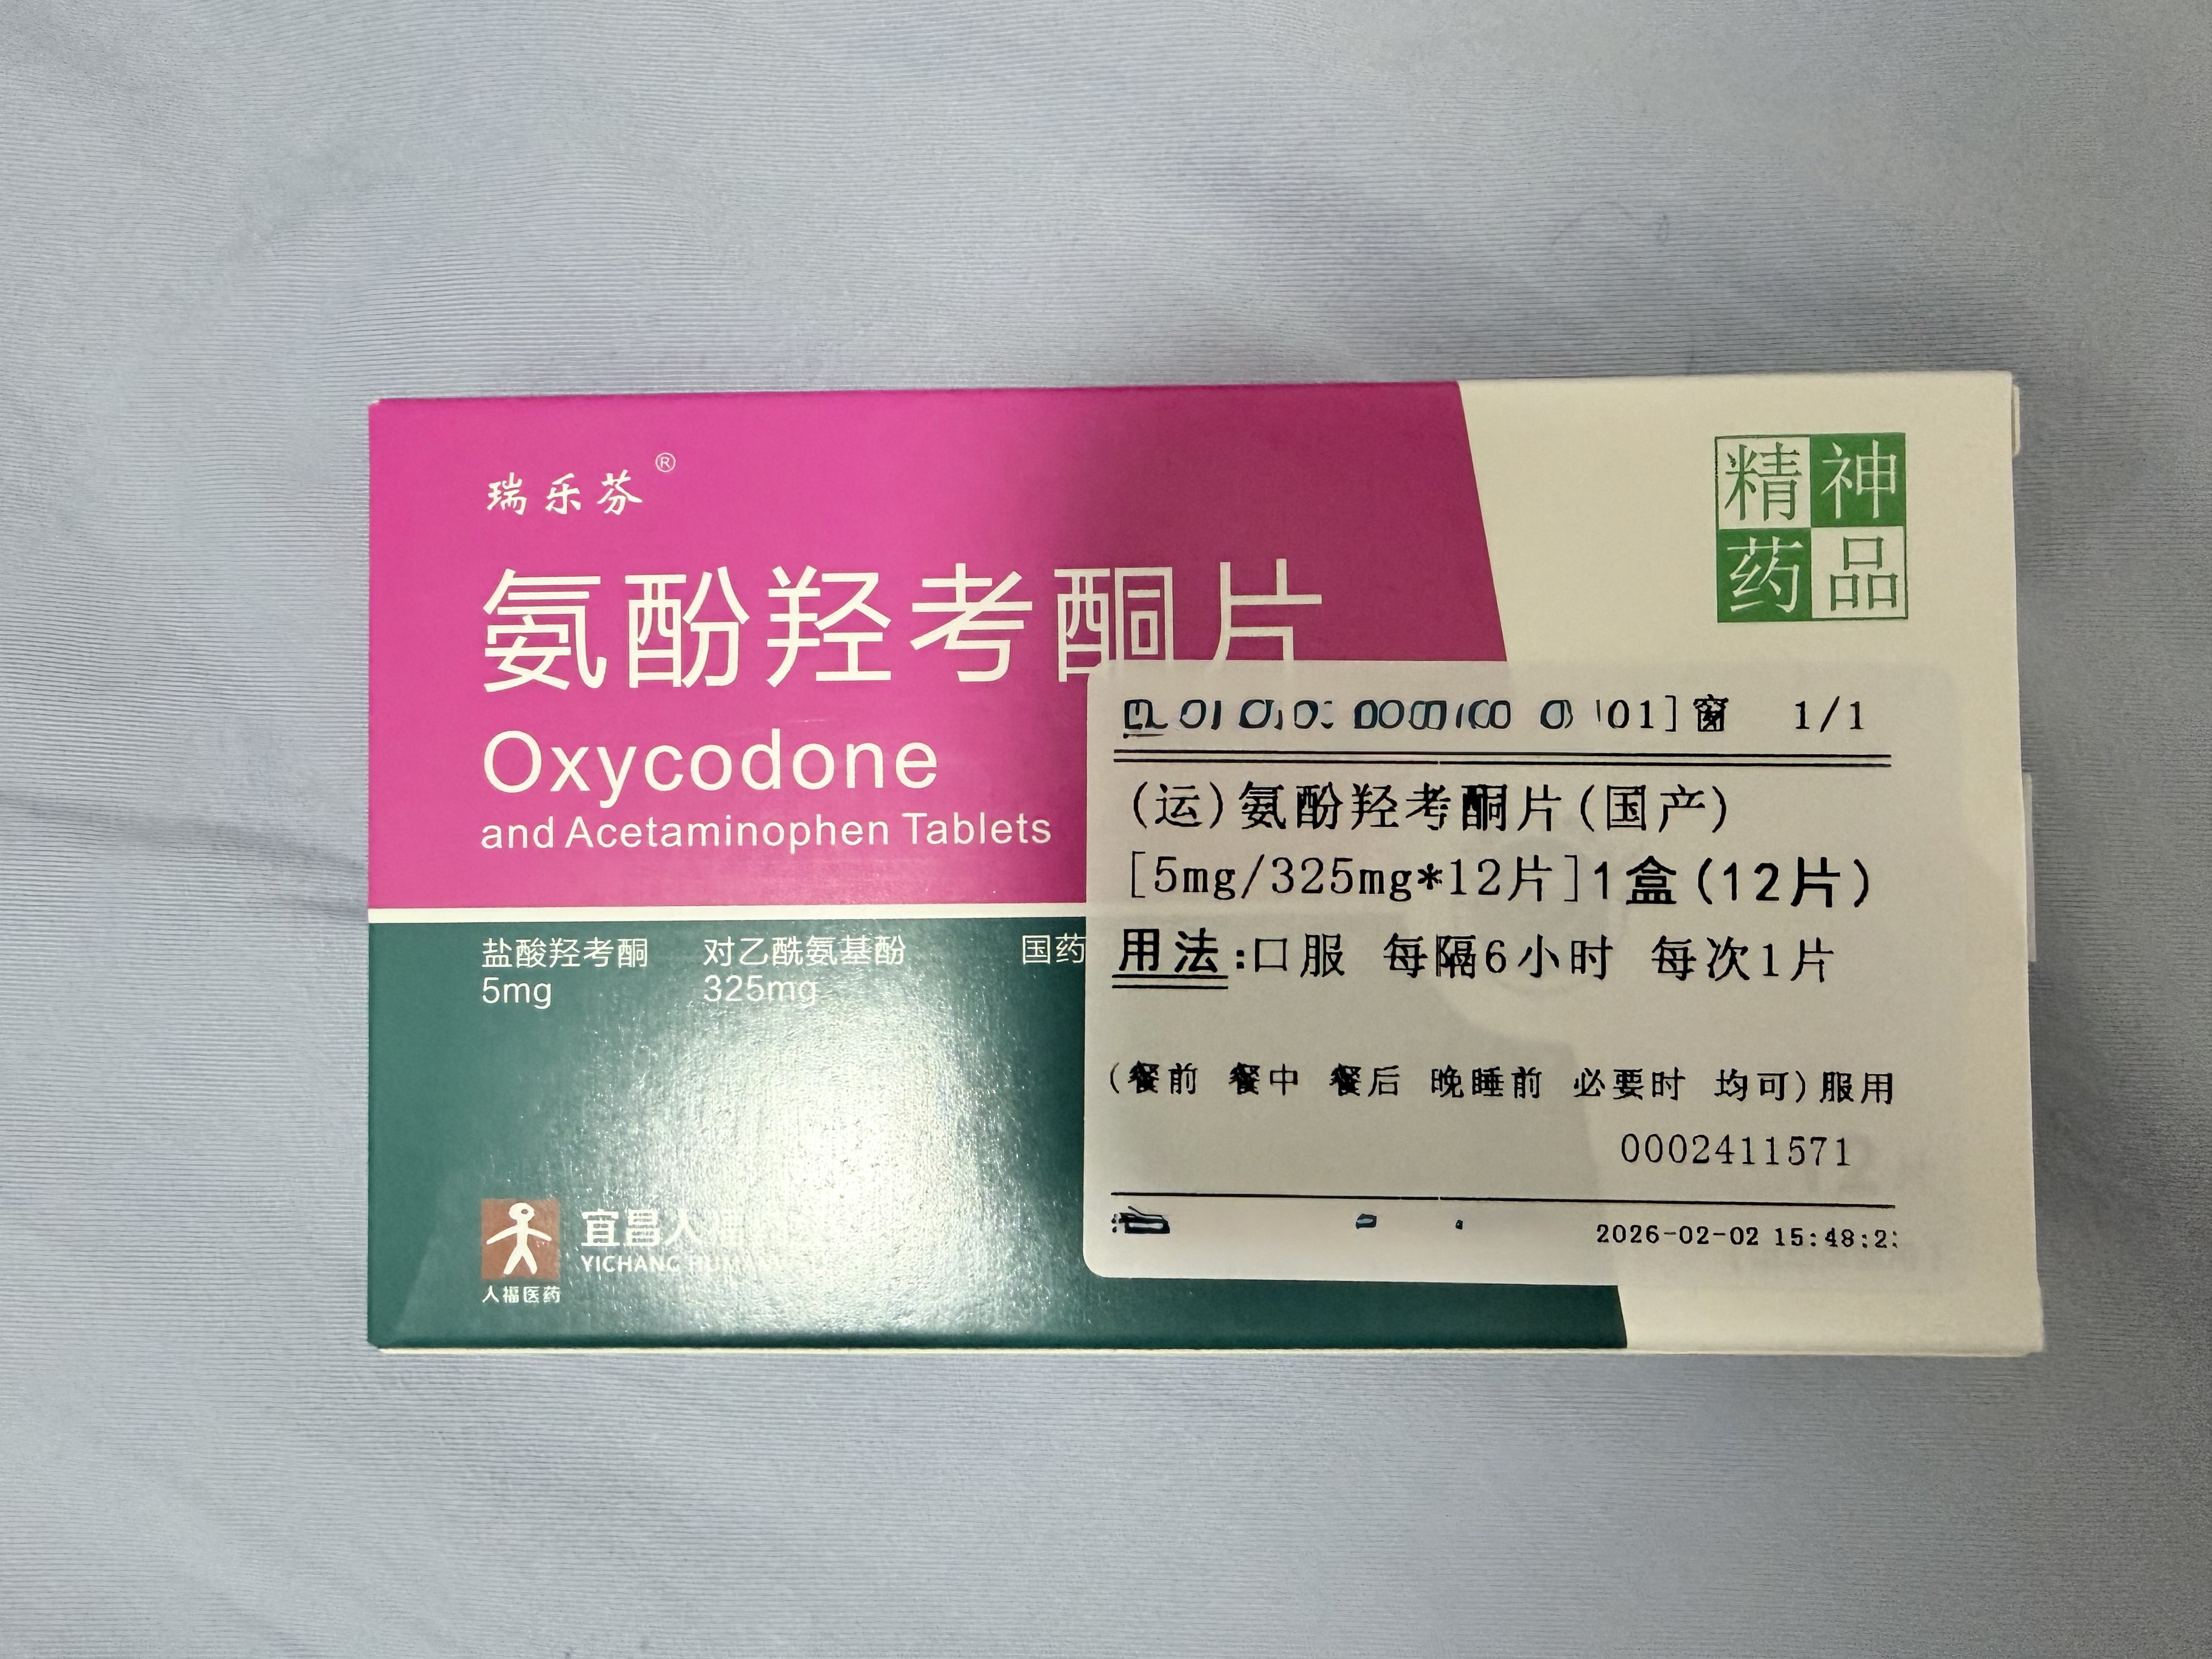

μ-opioid激动使我史无前例地健全…

多线程的同时专注度在线,动力max灵感up,焦虑抑郁一扫而空,交流能力和欲望↑↑

这样真的不好吗…?我不确定和代价比起来是否划算,但至少现阶段它为我提供了很大收益,而且光慢性疼痛消失了就已经很幸福了。

炽烈已极 @AnIncandescenceMOR可能因为耐受,第一次给药把受体占满了第二次几乎无效,羟考酮作用在压型κ的那一部分让头晕恶心更明显,几乎没有体会到什么正面作用,和之前被包裹在温暖和安心中停下呼吸也没有窒息感不同,它会让我困得撑不住又被呼吸暂停的缺氧憋醒,有点坏了

@Kumamushi2021 这个剂量的话,刚好卡在线上,然后肝损会抑制其他药物的代谢,你或许会在一段时间后绝望和痛苦地睁开眼睛……我经历过。这并非单纯劝阻你的行为,关于剂量和效应所言属实。

🥛💤 @Kumamushi2021@AnIncandescence 如果减少氨酚羟考酮的剂量,增加普瑞巴林和酒精的剂量呢……不过那样我可能会呕吐吧。有时候真恨自己不懂药理,连结束生命都要靠赌。

有救了..!但是和auv冲突了…cyp2d6被ban的不剩一点,吃个dxm能晕完第二天。陷入沉思…

炽烈已极 @AnIncandescence@hami0721 但是。连病人都知道至少要管理症状,国内医生就是很不乐意开阿片类止痛药。别说阿片了,之前我去看那么多次连个普瑞巴林都没开过,就瞅着那几个对乙酰氨基酚布洛芬双氯芬酸,至少试个强一点的非甾体抗炎药啊气死我了(`へ´)

找值班医生护士开药,因为平常自己吃的没带过来,优先就考虑了曲马多(口服/注射),我说和我抗抑郁药cyp2d6冲突了

医:那羟考酮?(发愁)你用的药这么多怎么全是冲突 https://t.co/6fs24OppyL

炽烈已极 @AnIncandescence我说不用那么强的也可以,医问加巴喷丁?我说弱了……于是目的达成,开了pr75